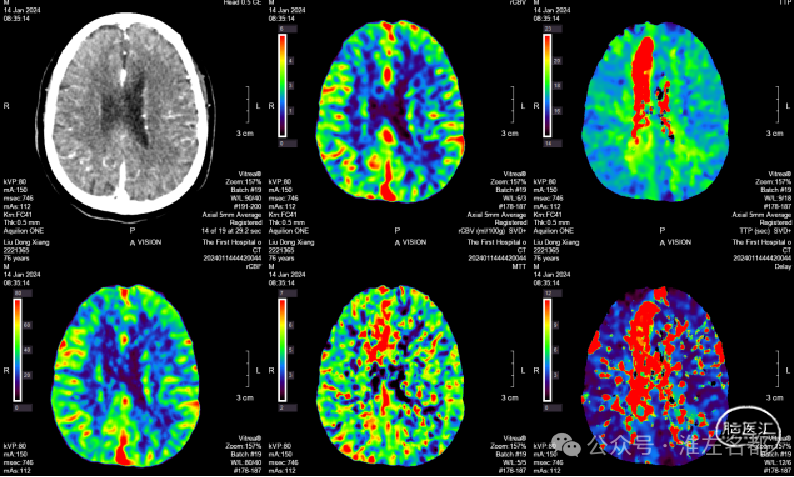

2024-01-15

复查多模式CT

CT平扫:少量蛛网膜下腔出血已基本吸收;胼胝体膝部和右侧额顶叶小梗死低密度影。

CTA:右侧大脑前动脉A2局部管腔轻微狭窄。

脑CTP:双侧半球血流灌注基本对称,右侧额叶内侧局部TTP增快。